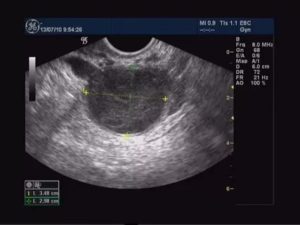

- УЗИ органов малого таза. Во время процедуры изучают матку и ее шейку, мочевой пузырь, придатки. Это позволяет обнаружить опухоли, определить их размеры и локализацию, выявить сопутствующие патологии.

- УЗИ с вагинальным датчиком, который позволяет произвести качественное обследование гинекологических органов.

Киста на ультразвуковом исследовании

Во время проведения обследования эндометриоидной кисты на аппарате УЗИ, она представляет двухслойную капсулу с содержимым и напоминает кисту желтого тела. Это служит поводом к повторному исследованию, так как киста желтого тела, в отличие от эндометриоидной кисты яичника, способна рассасываться самостоятельно, не прибегая к лечению и избегая операции.